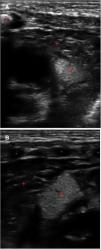

Magnetic resonance imaging of the head at 6 days post birth. Axial turbo spin echo (TSE) sequence T2-weighted images (A and B), axial T1 inversion recovery (T1IR) sequence image (C and D) Coronal T1-weigthed 3D image (E), sagittal T1-weighted 3D image (F), sagittal TSE T2-weighted image (G) and sagittal T1-weighted 3D following intravenous contrast administration (H). Visualization of cortical tubers that appeared hypointense on T2-weighted imaging and hyperintense on T1-weighted images (yellow arrows in A and C), radial migration lines in white matter (blue arrows in A, C and F), subependymal nodules (red arrows in B, D, E and F) and white matter cysts that appear hyperintense in T2-weighted images and without enhancement after contrast administration (green circle in G and H). The colour features of the figures can only be discerned in the digital version.

We present the case of a term newborn infant that underwent a bedside ultrasound examination of the chest due to respiratory distress. Transverse-plane scanning with a linear probe can be used to rule out pneumothorax,2 and in this patient it revealed several well-demarcated hyperechoic lesions up to 2 cm in diameter confined to the myocardium (Fig. 1, Appendix B, supplemental material). The lung parenchyma presented an interstitial pattern in a gradient with a thin pleural line and lung sliding, compatible with transient tachypnoea (respiratory support for 48 h). The echocardiogram confirmed the presence of cardiac tubers, and a brain magnetic resonance evidenced subependymal tubers and nodules (major criteria), radial migration lines, subependymal nodules and cysts in the white matter (Fig. 2) which, combined with the results of genetic testing, led to the diagnosis of tuberous sclerosis type 2 (Bourneville syndrome, pathogenic TSC2 gene variant).